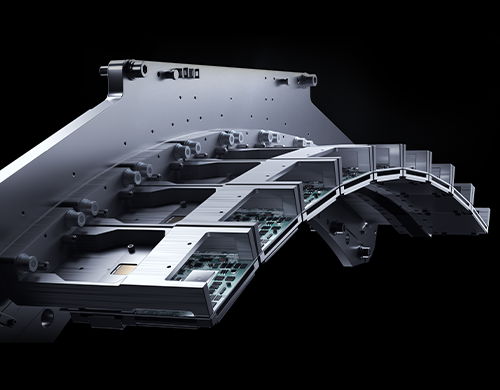

提供多种血管提取和中心线编辑工具,辅助诊断血管狭窄程度

支持结肠分割、中心线提取以及内窥图生成,高效获取结肠结构信息

多维度对肺部支气管、肺泡等实质结构进行量化评估与病变识别,帮助医生全面了解患者肺部健康状况

一键肺结节筛查可提升血管旁、磨玻璃等易漏结节识别效能,量化多维结节数据,助力肺病早筛早治

牙齿全景图、剖面图显示与神经通路标记,助力全面洞察齿科状况、科学制定齿科治疗方案

帮助快速识别并标记肋骨,一键实现肋骨平铺、展开、分割功能,提升骨科诊断效率